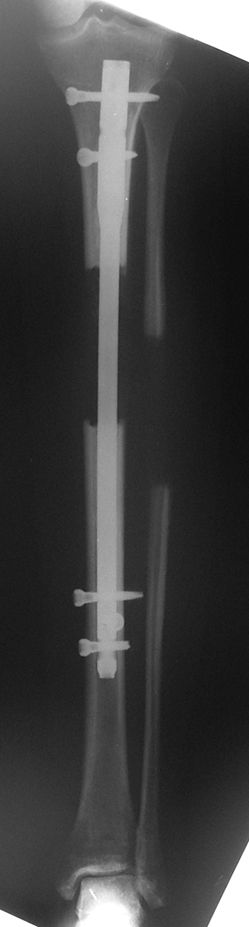

Biz son zamanlarda, seçilmiş vakalarda, uzatma sonrası uzunluğu ve “alignment’ı” korumak amacı ile unilateral dinamik aksiyel fiksatör ve kilitli intramedüller çivi kombinasyonunu tercih etmekteyiz. Bu yöntemin ön şartları medullanın en dar çapının 7 mm.’den geniş olması ve uzatma sonrası distalde en az 8 cm. uzunluğunda çivi kalabilmesidir. İntramedüller çivi hem uzatma esnasında femurun üzerine gelen makaslama ve bükülme kuvvetlerini nötralize etmekte hem eksternal fiksasyon süresini kısaltmakta, hem de yeni oluşan kemiği kırıklara karşı korumaktadır. Serimizde bir vakada subtrokanterik femoral osteotomi yapılmıştır. İntramedüller çiviye rağmen varus angulasyonu oluşması yönünde bir dezavantaj tespit etmedik.

İlizarov, distraksiyon osteogenezisi için endosteal kan dolaşımının önemini vurgulamıştır. Biz tüm vakalarımızda femuru oyarak intramedüller çiviyi çaktık; buna rağmen hiçbir vakada kallus oluşma süresi tahminimizden daha uzun olmadı. Bu yüzden medüller dolaşımın bozulmasına bağlı yeni kemik oluşma hızında bir yavaşlama olmadığını düşünüyoruz. Oyma sonrası meydana gelen revaskülarizasyon, intramedüller çivili fiksasyon stabilitesi ve erken fonksiyonel yüklenme bu gerçeğin temelini oluşturmaktadır. Eksternal ve internal fiksasyon yöntemlerinin kombine kullanımının potansiyel dezavantajları kan kaybının artması, intramedüller infeksiyon, yağ embolisi olasılığı ve aşırı metal yüküdür. Bunların içinde en çok korkulan problem bir çivi dibi infeksiyonun tetikleyeceği derin intramedüller infeksiyondur (panosteomyelit). Bizim serimizde bu yönde hiçbir komplikasyon gelişmemiştir. Bu olası komplikasyonun önlenmesi amacı ile uzatma sonundaki kilitleme medialden yapılmalıdır; ayrıca intramedüller çivi ve eksternal fiksasyon pinlerinin teması önlenmelidir.

İntramedüller çivi ve eksternal dinamik aksiyel fiksatör kombinasyonu teknik olarak standart İlizarov uygulamalarından daha zordur. Ancak şu avantajlar yöntemi cazip hale getirmektedir; eksternal fiksasyon süresinde kısalma, refraktüre karşı korunma, erken rehabilitasyon, azami hareket genişliği kazanma ve günlük yaşam konforu. Bu avantajlar artan maliyet , artan kan kaybı ve potansiyel derin infeksiyon gibi dezavantajların önüne geçmektedir. Sonuç olarak, bulgularımızın eşliğinde, intramedüller çivi üzerinden femoral uzatma tekniğinin güvenilir ve dayanıklı bir metod olduğunu ve bizce standart İlizarov uygulamalarına üstünlük sağlayan avantajlar getirdiğini söyleyebiliriz.